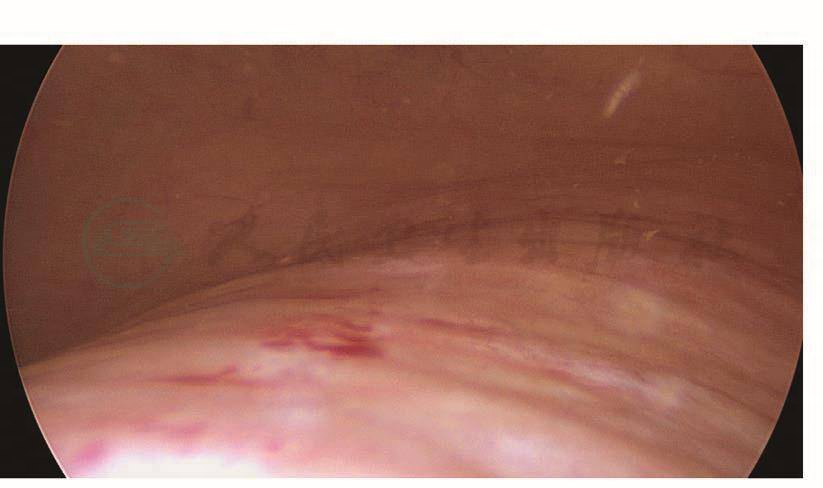

如果术中无法确认输尿管是否损伤,可以考虑在结束手术前进行膀胱镜检查,观察输尿管出口的喷尿情况。膀胱镜下先找到膀胱黏膜,在膀胱底部找到突出的部位,此处即为膀胱三角区,输尿管出口位于其两侧。有时候输尿管蠕动的间隔比较长,必要时可以静脉注射呋塞米20mg,促进输尿管蠕动、喷尿。如果观察到两侧输尿管出口正常蠕动并有喷尿,说明输尿管没有断裂性损伤,但不能排除热损伤(图117~图120)。

图117 膀胱三角区

图118 左侧输尿管出口

图119 右侧输尿管出口

图120 输尿管出口喷尿